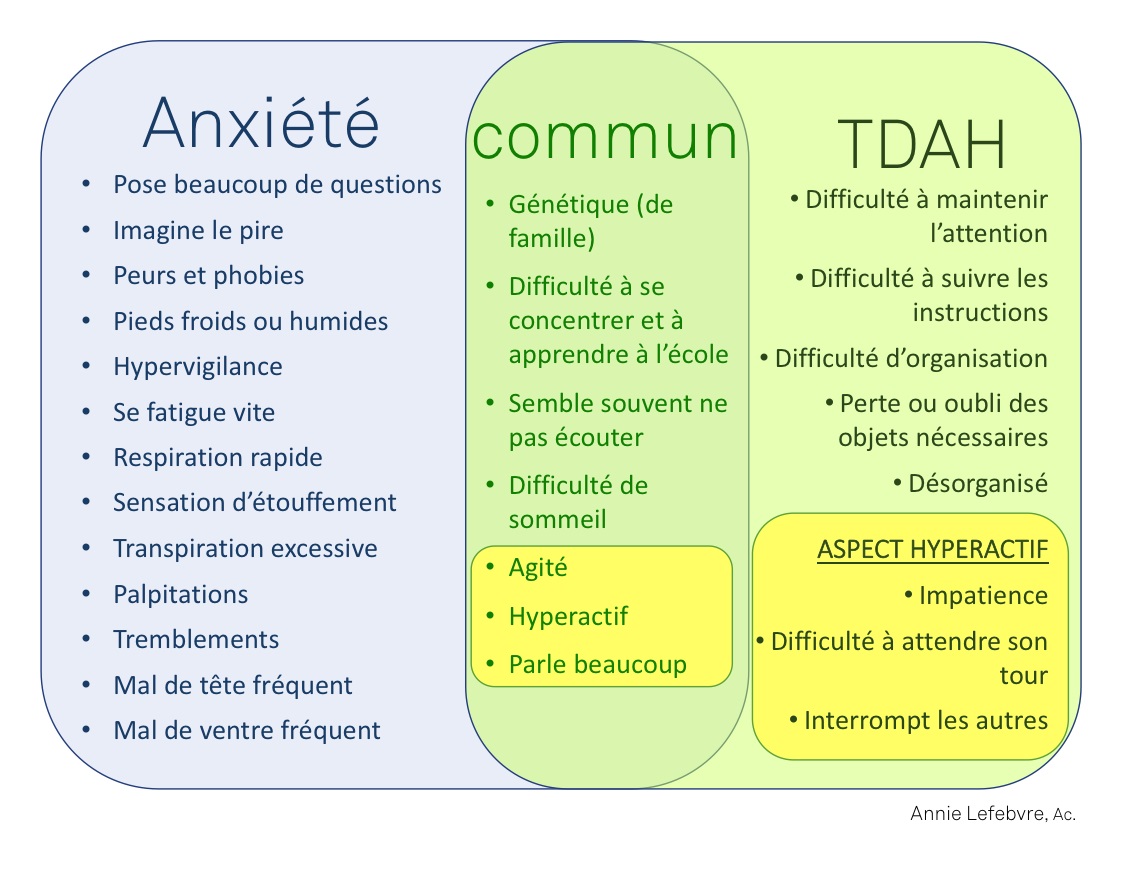

Anxiété de performance Crises d’angoisses, Stress  Points communs et différences entre le TDAH et l’Anxiété  Cliquez pour agrandir |

► L’inquiétude chez eux se traduit souvent par une anxiété